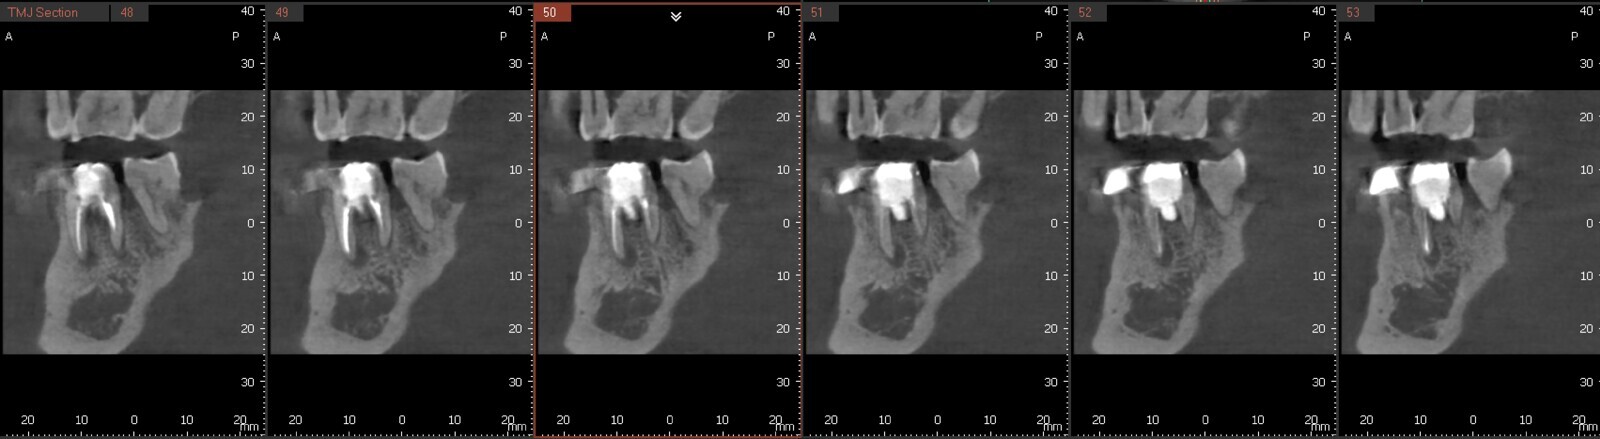

Fig.2a: Pre-op CBCT images of tooth #46: No obturation material in the distal and mesiobuccal canal (a); scanty obturation of the canals and breach of the floor of the pulp chamber, no obturation beyond a few millimetres down the orifice (b & c); radiolucency in the furcation area and periapical region of both roots (d -g).

Fig.2b: Pre-op CBCT images of tooth #46: No obturation material in the distal and mesiobuccal canal (a); scanty obturation of the canals and breach of the floor of the pulp chamber, no obturation beyond a few millimetres down the orifice (b & c); radiolucency in the furcation area and periapical region of both roots (d -g).

Fig.2c: Pre-op CBCT images of tooth #46: No obturation material in the distal and mesiobuccal canal (a); scanty obturation of the canals and breach of the floor of the pulp chamber, no obturation beyond a few millimetres down the orifice (b & c); radiolucency in the furcation area and periapical region of both roots (d -g).

Fig.2d: Pre-op CBCT images of tooth #46: No obturation material in the distal and mesiobuccal canal (a); scanty obturation of the canals and breach of the floor of the pulp chamber, no obturation beyond a few millimetres down the orifice (b & c); radiolucency in the furcation area and periapical region of both roots (d -g).

Fig.2e: Pre-op CBCT images of tooth #46: No obturation material in the distal and mesiobuccal canal (a); scanty obturation of the canals and breach of the floor of the pulp chamber, no obturation beyond a few millimetres down the orifice (b & c); radiolucency in the furcation area and periapical region of both roots (d -g).

Fig.2f: Pre-op CBCT images of tooth #46: No obturation material in the distal and mesiobuccal canal (a); scanty obturation of the canals and breach of the floor of the pulp chamber, no obturation beyond a few millimetres down the orifice (b & c); radiolucency in the furcation area and periapical region of both roots (d -g).

Fig.2g: Pre-op CBCT images of tooth #46: No obturation material in the distal and mesiobuccal canal (a); scanty obturation of the canals and breach of the floor of the pulp chamber, no obturation beyond a few millimetres down the orifice (b & c); radiolucency in the furcation area and periapical region of both roots (d -g).